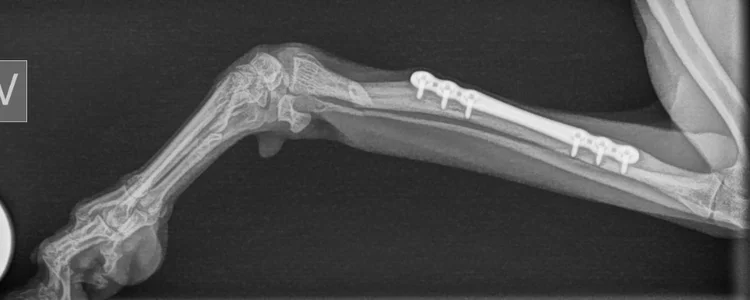

Han er bare ett år gammel, men har allerede opplevd å brekke beinet sitt to ganger. Denne gangen er bruddet mer komplisert.

Første beinbrudd skjedde da han var bare 3 måneder gammel. Den gang fikk han operert inn skruer og metallplate i beinet, og etter kort tid var han tilbake igjen som normal!

Nå har han altså vært så uheldig og brukket det samme beinet igjen. Han skulle bare hoppe ned fra sofaen, og denne gangen gikk det feil.

Vi står derfor ovenfor et mye mer komplisert brudd nå. Gammel metallplate må fjernes, og det må settes inn en ny. Dette krever spesialisert ortopedisk kompetanse.